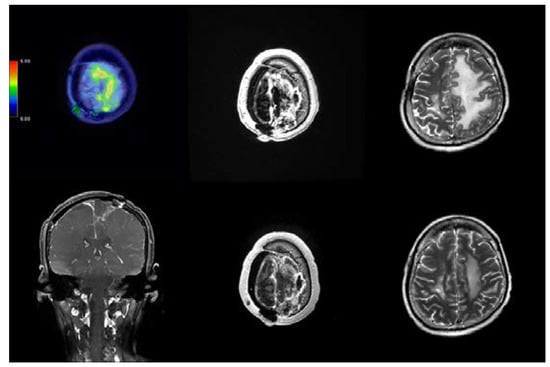

2.2. Case 191

| 191 | 12 January 2022 15 June 2022 | 910 1055 | 39.15 35.34 | 18.99 18.96 | 11.59 12.48 | PR SD | 13 December 2022, PR | 11 |

| 191 | 45/Male | Atypical meningioma | Right high frontal | 3.9 | RT + OP + ChemoT |